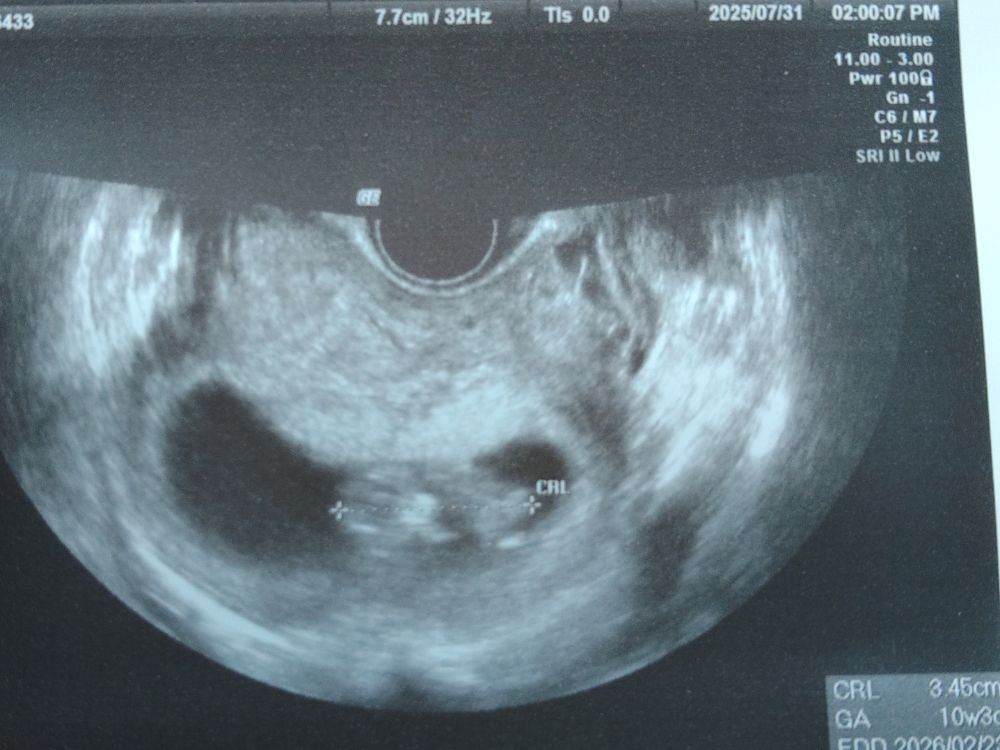

7月に里帰りして、初めて病院に行き、胎嚢・心拍を確認できたときにも安心はできませんでした。

特に妊娠12週頃までは「次の検診まで大丈夫かな」と毎日ドキドキして過ごしていました。